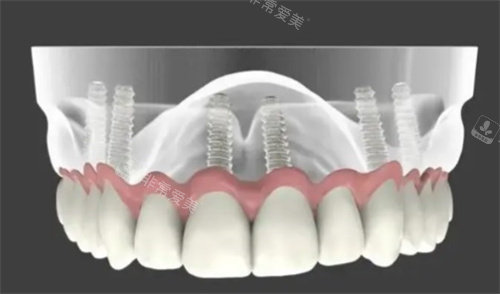

全口种植

All - on - 4 半口 55000 起(注:此为整体价格,非单颗价格),4 颗植体支撑 12 颗牙冠。

医院引进了德国原厂智能化种植系统和 3D 导板导航技术。

通过 CT 扫描定位牙槽骨,能将手术误差控制在 0.1 毫米内。

就好比给医生装上了“导航仪”,让种植手术更加比较准、靠谱。

在种植牙过程中,能比较准避开神经血管,真正实现“当天种牙当天用”。